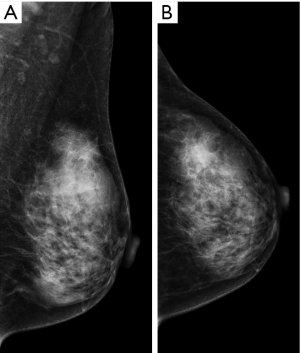

Mammography of the breast showed a partially obscured mass with some margins visible (approximately 2.0 cm × 1.7 cm) (Figure 1). The patient also underwent an ultrasound examination, which revealed a hypoechoic, heterogeneous solid mass with indistinct borders measuring approximately 30 mm × 13 mm × 20 mm. The mass was located at the 12 o’clock position, approximately 4 cm from the left nipple, and involved the subcutaneous layer (Figure 2A). According to the Breast Imaging Reporting and Data System (BI-RADS) classification, this lesion is considered to be in the 4C category (12). Color Doppler ultrasound showed blood supply within the mass (Figure 2B). Multiple solid nodules were observed in the remaining areas of both breasts (BI-RADS category 3).

Figure 1 Radiographic examination results. (A,B) The mammography showed a high-density mass with obscured boundaries: (A) mediolateral oblique view; (B) craniocaudal view.